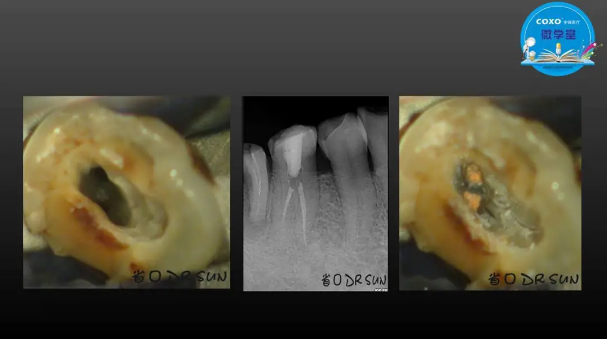

主講:孫書昱

主任醫(yī)師,牙體牙髓副主任, 廣東省口腔醫(yī)院牙體牙髓科 主任醫(yī)師。2003年碩士研究生畢業(yè),研究方向為牙體牙髓病學,擅長于牙體牙髓病的診斷、齲齒、牙髓炎、根尖周病的治療以及前牙美容修復。